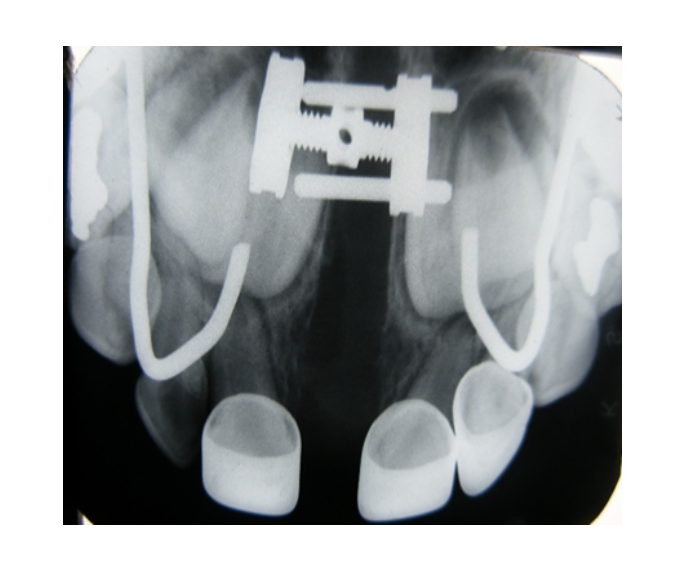

Mordida cruzada posterior bilateral